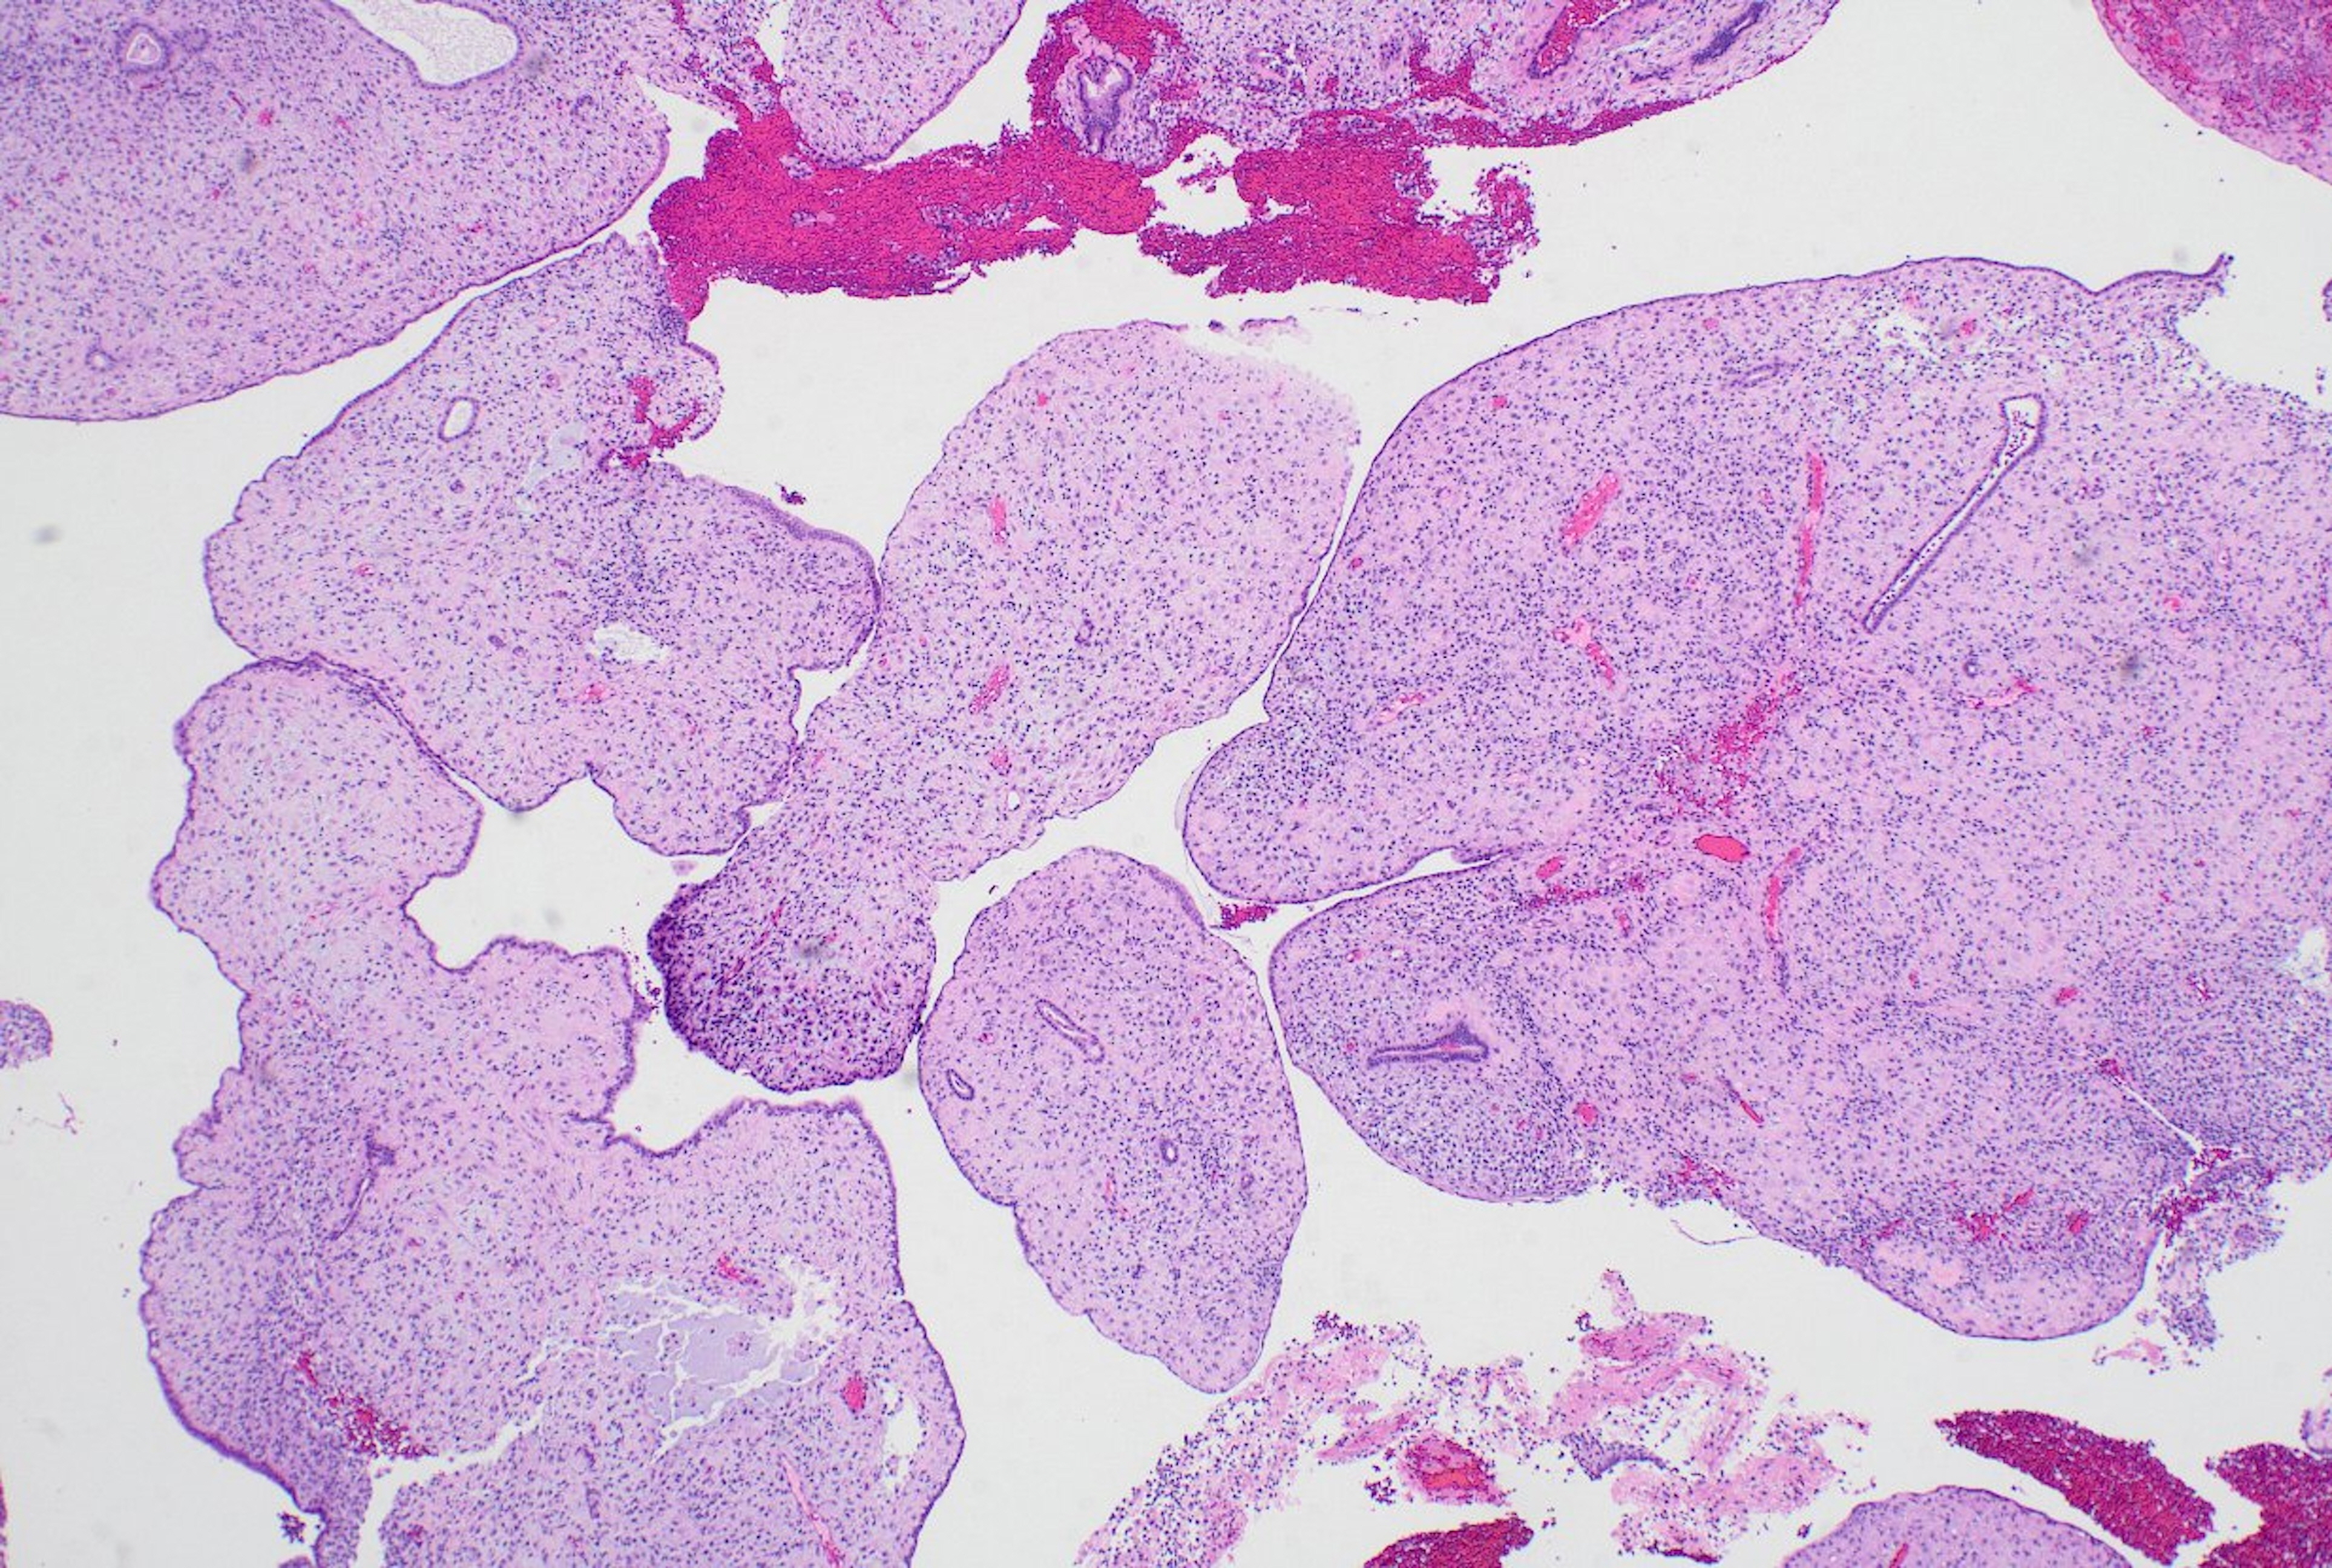

Fig. 3.

Large bulbous, polypoid structures with prominently pseudodecidualized stroma were not classified as displaying papillary architecture for the purposes of this study, given that it is well recognized that such structures are common endometrial alterations associated with exogenous progestins in non-hyperplastic endometrium.

jptm-2025-09-12f3.jpg